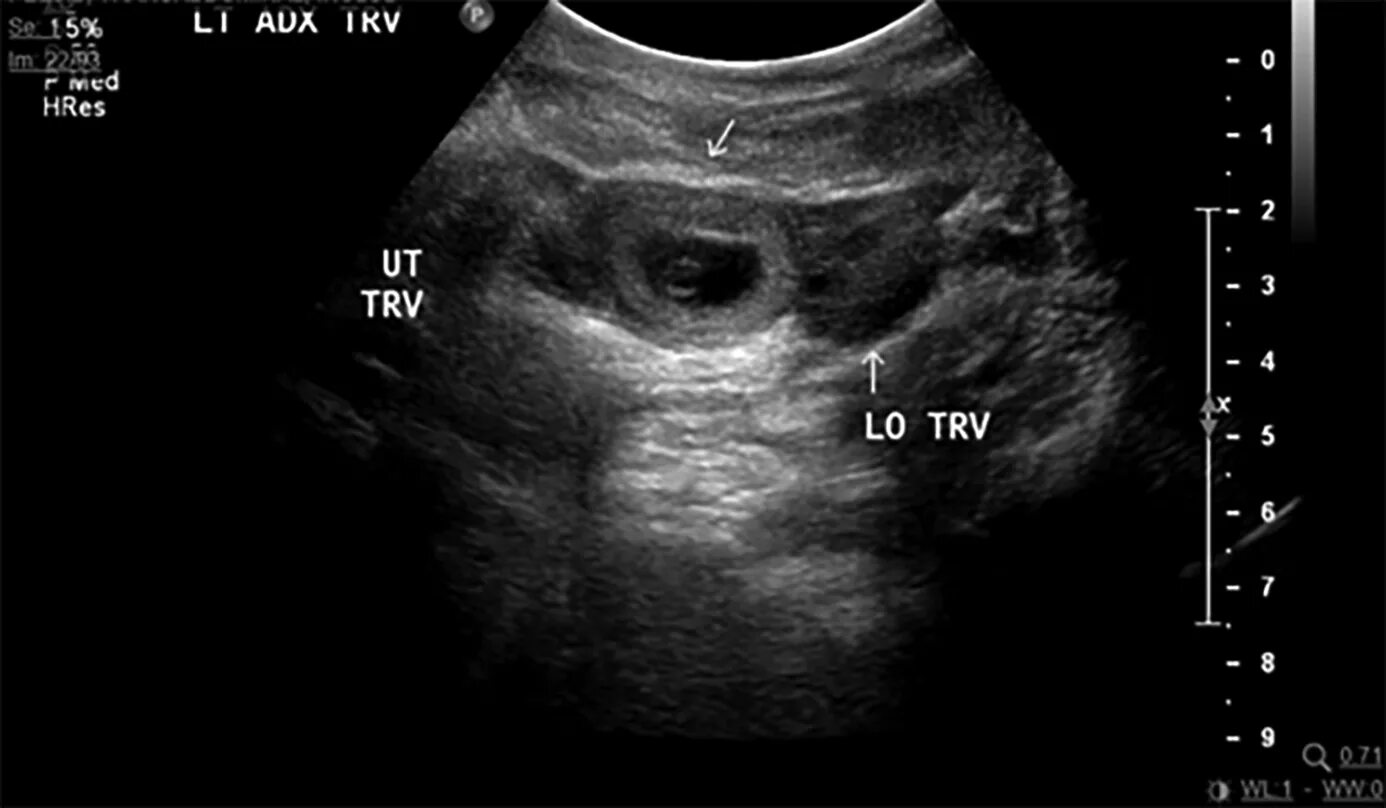

Можно ли на узи увидеть внематочную беременность